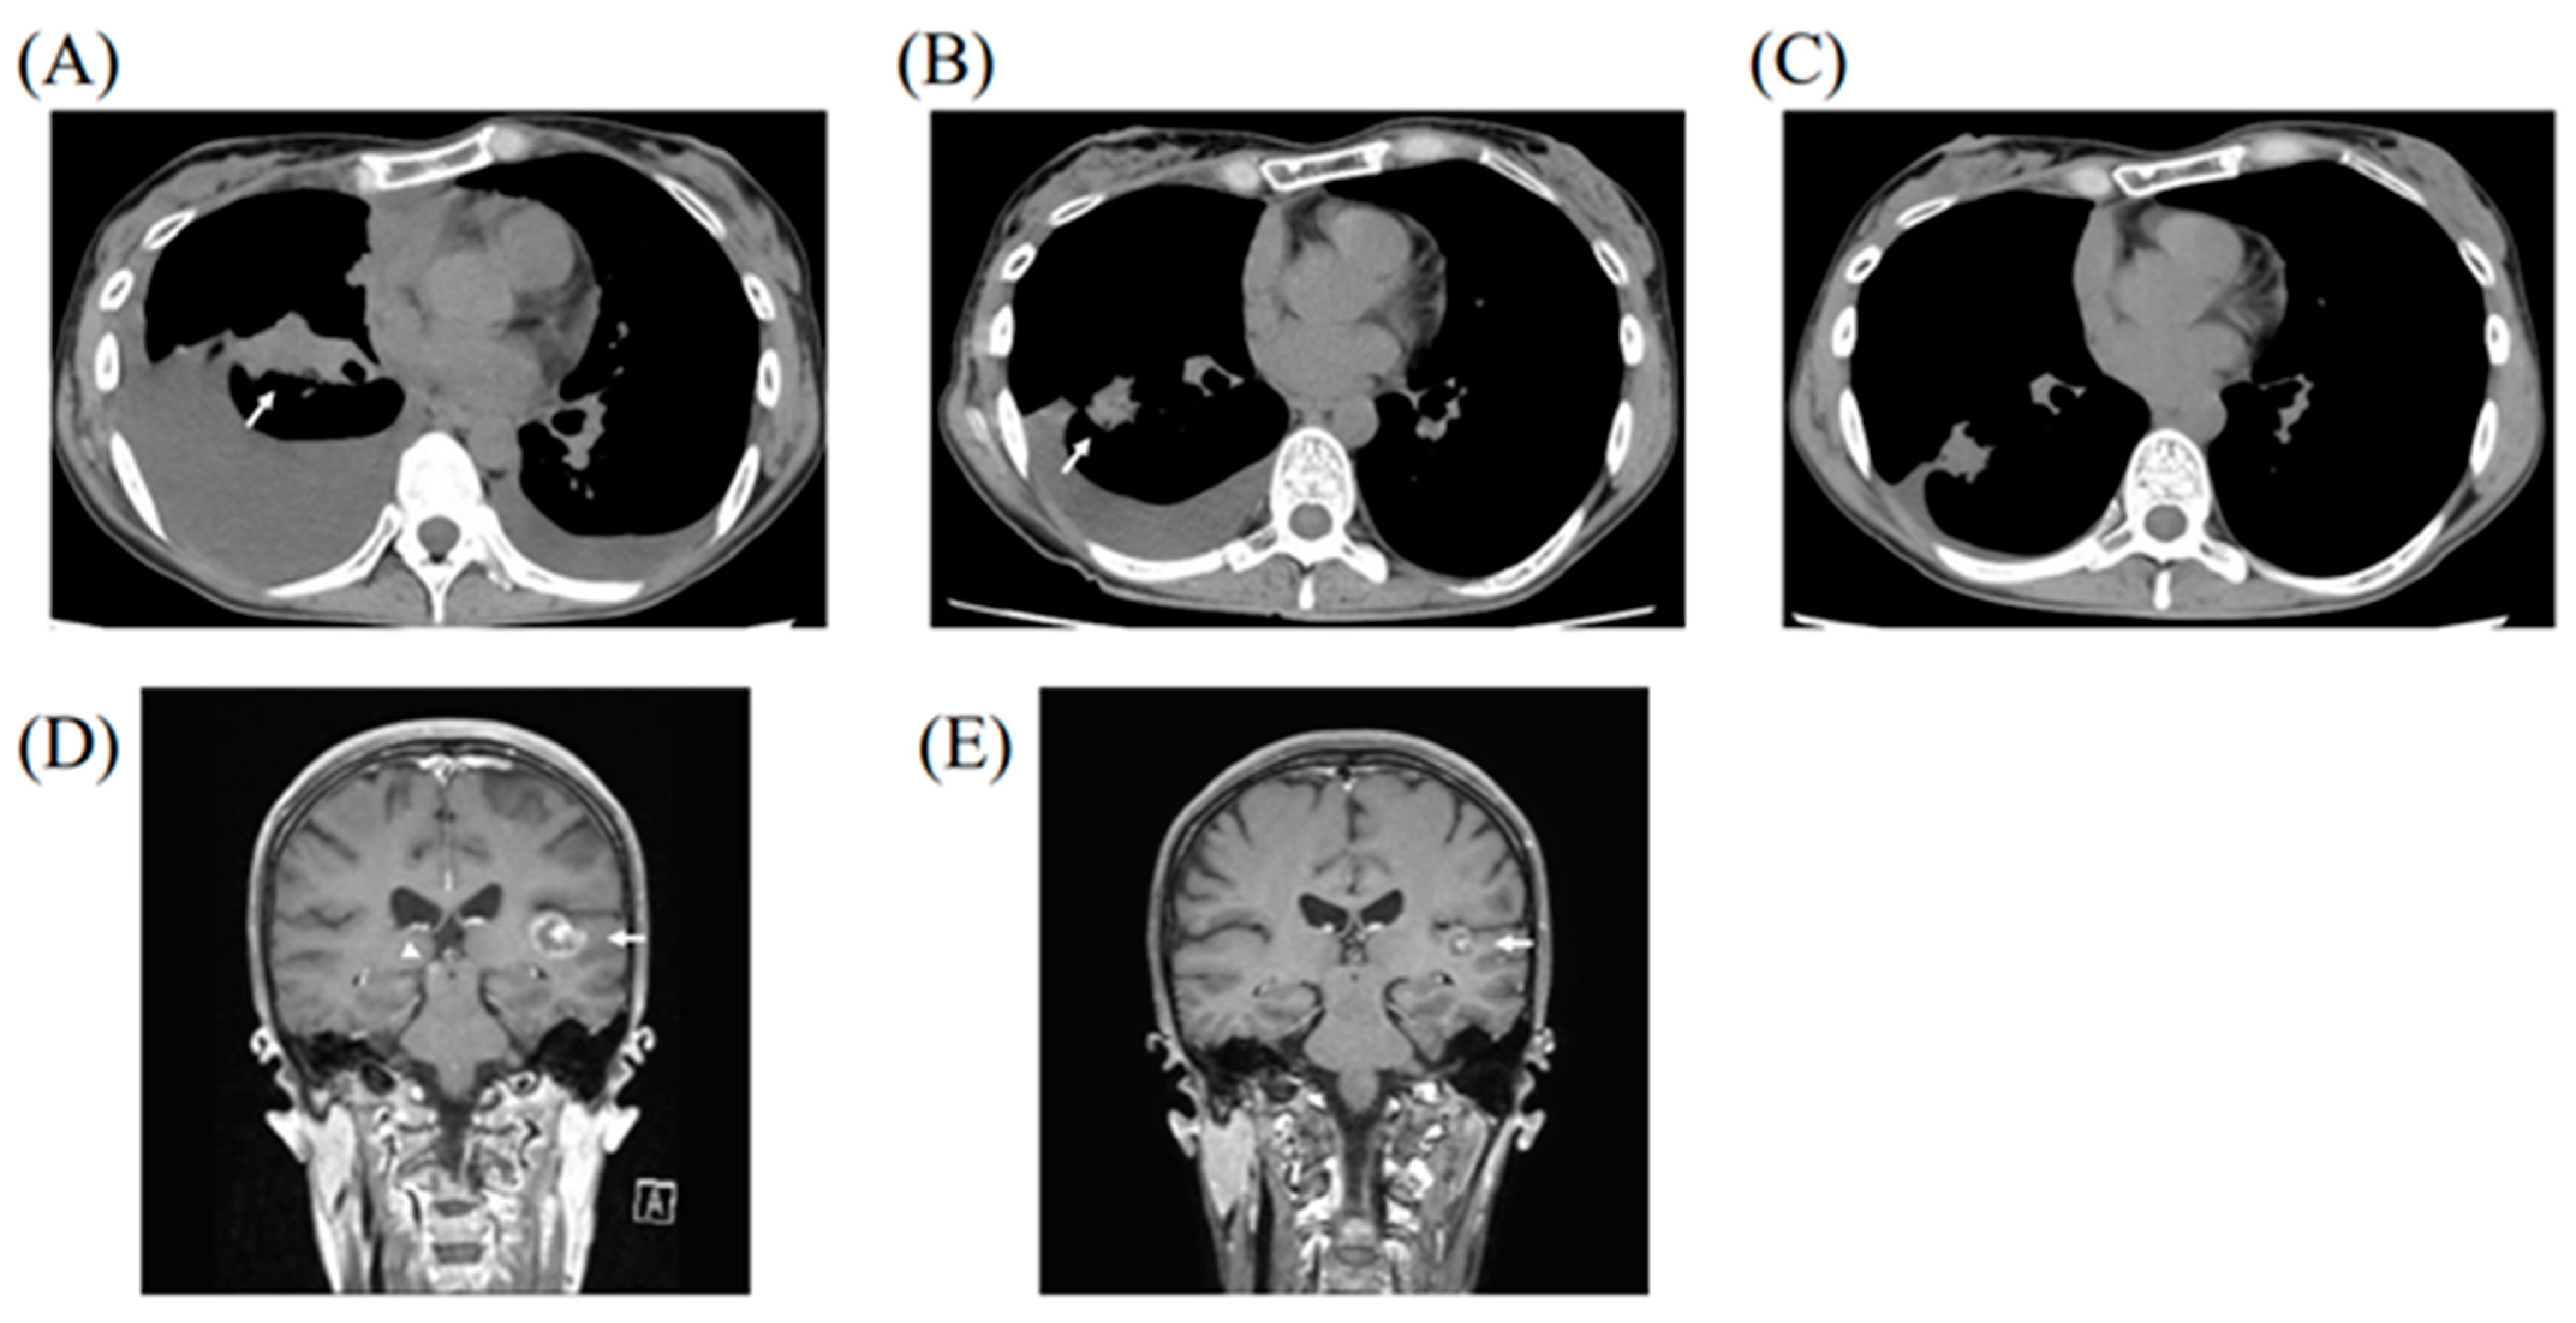

2. Case Report